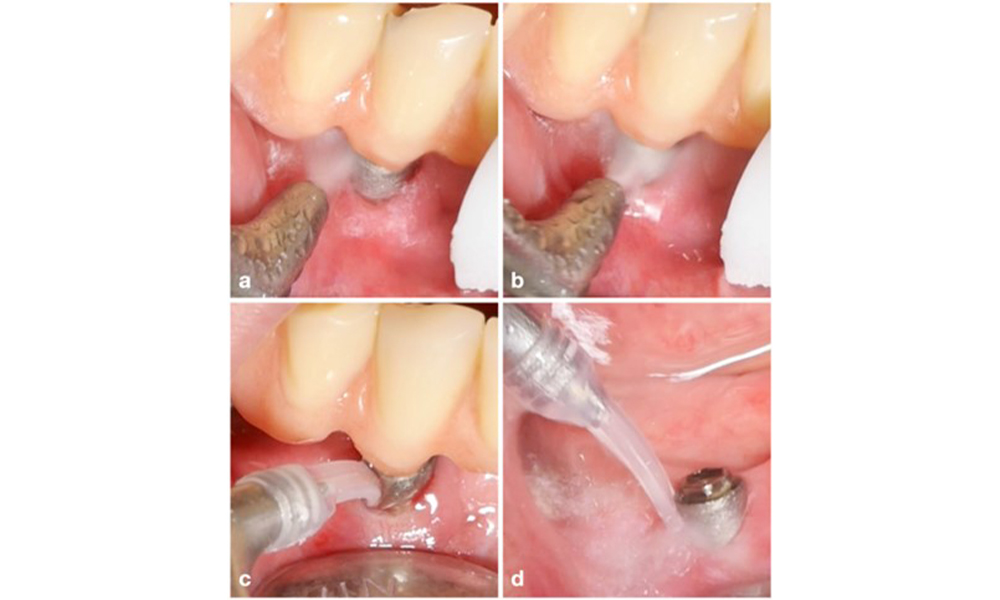

Management of peri-implantitis at implants judged as treatable consists of a non-surgical phase, which is often followed by surgical intervention. For the non-surgical approach, similar measures as those applied for the treatment of peri-implant mucositis are used; based on laboratory experiments air-polishing devices with a subgingival nozzle appear to provide certain advantages in terms of biofilm removal, compared to hand- or ultrasonic instruments (Herrera et al. 2023; Moharrami et al. 2019; Ronay et al. 2017) (figure 9).

Yet, the non-surgical approach often has limitations in accessing the implant surface, leading to insufficient decontamination. This is indeed reflected in the clinic, where disease resolution after non-surgical treatment of peri-implantitis is rather unpredictable and recurrence is observed for most cases, i.e., disease resolution was reported to occur only in less than every second case (Ramanauskaite et al. 2021). Therefore, the outcome of non-surgical treatment needs to be evaluated after about 6 weeks, and in cases of moderate or advanced peri-implantitis, surgery should be expected.